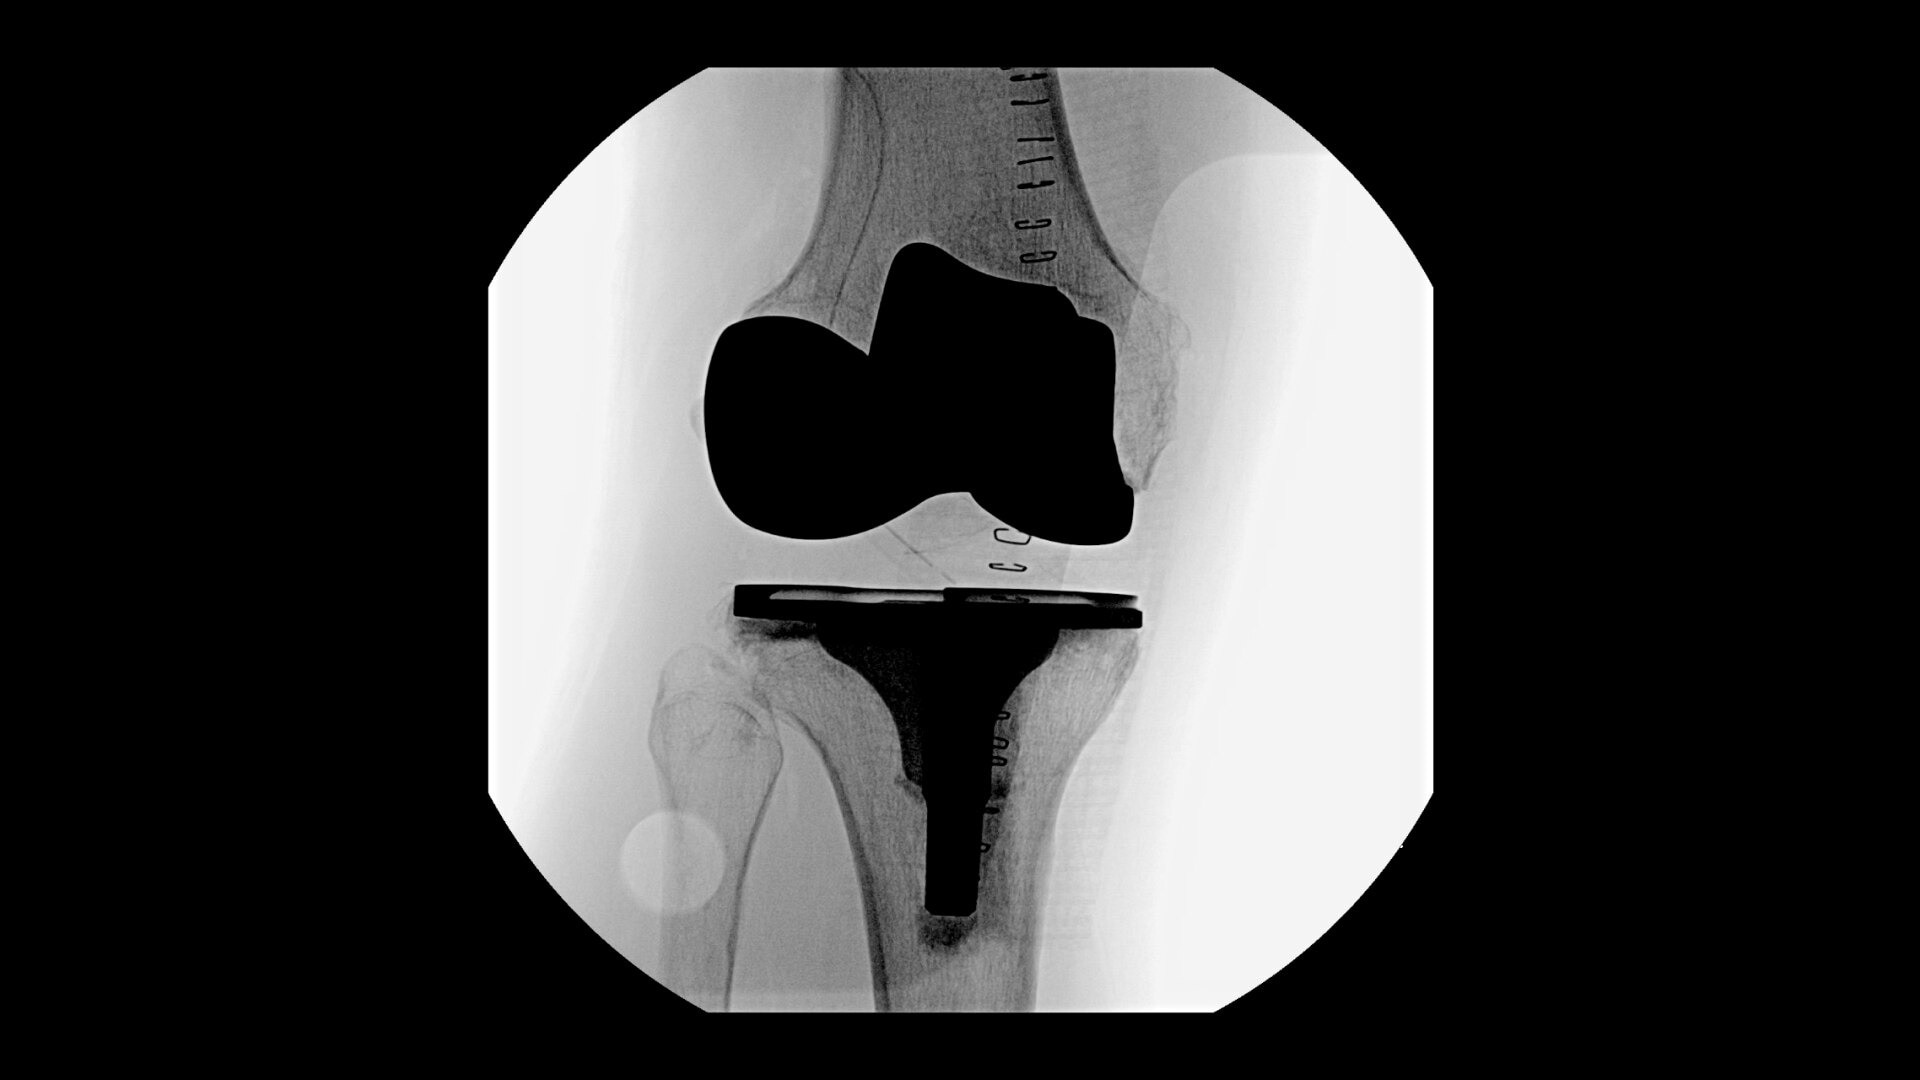

Complex orthopedic procedures require powerful imaging systems. OEC premium C-arms perform in a variety of procedures such as:

• Knee replacement